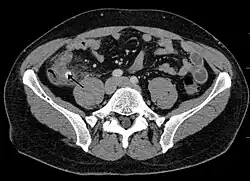

-

Appendicolith as seen on CT -